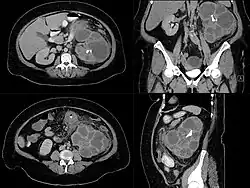

Die Diagnosestellung kann recht schwierig sein, Hauptdifferentialdiagnose ist das Nierenkarzinom. Nicht selten wird die Diagnose erst in der Gewebsuntersuchung gestellt.[2] Im Urinsediment Leukozyturie, Bakteriurie und manchmal Xanthomzellen, im Blutserum Leukozytose, erhöhte BSG und erhöhtes CRP. Teilweise oder komplett tumorartig vergrößerte Niere bei erhaltenem anatomischem Aufbau mit unregelmäßig erhöhter Echogenität im Nierenultraschall, im AUR fehlende oder stark verminderte Ausscheidung.[10] Nierensteine können vorliegen. Die präoperative Abklärung umfasst Computertomografie und/oder Magnetresonanztomographie, letztere bei Kindern und bestehender Niereninsuffizienz.[2][4]